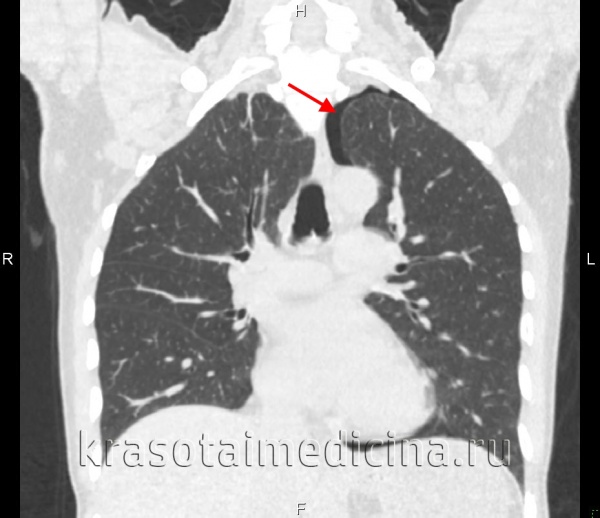

По данным томографии в правой плевральной полости имеется большое количество жидкости — до уровня второго ребра.